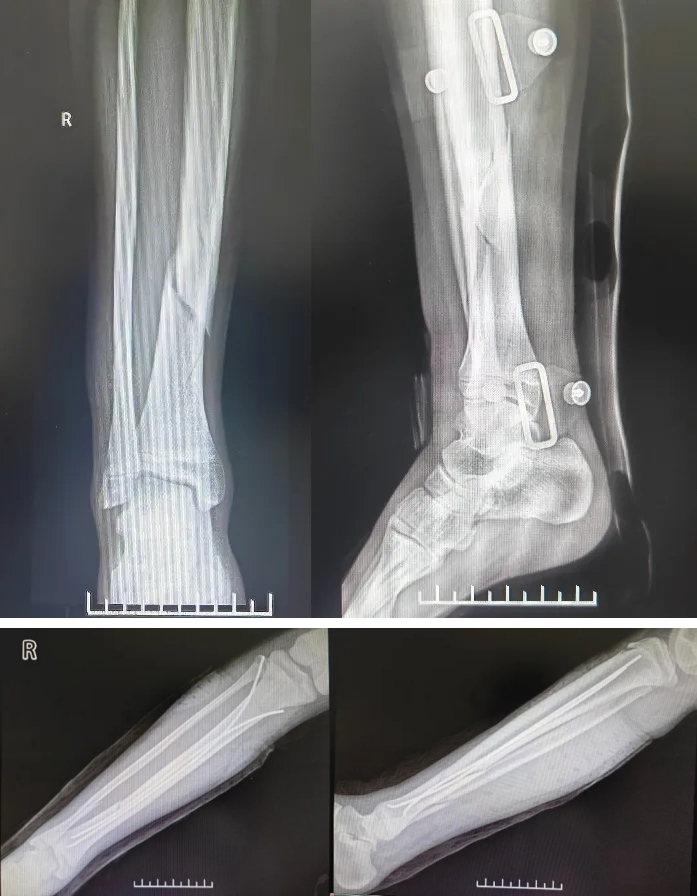

近日,山西省医院协会常务理事单位——太原市第二人民医院骨科在山西省著名小儿骨科专家黄永波教授指导下,首次使用弹性髓内钉技术,为一名12岁胫骨粉碎性骨折患者成功进行治疗。

患儿因剧烈运动导致胫骨粉碎性骨折,到太原市第二人民医院求治。骨科主任刘建国组织团队医护人员对患者的病情进行全面讨论,制定详细的治疗方案,考虑到患者为青少年,为减少局部创伤,决定行弹性髓内钉内固定术,并邀请山西省著名小儿骨科专家黄永波教授进行手术及指导。术前,黄永波教授与刘建国主任共同对患儿病情进行评估并制定手术方案。患者于2024年7月17日进行手术,7月23日出院。

▲患者术前(上)、术后(下)影像检查。